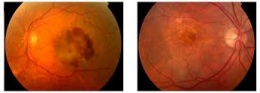

DMAE seca.jpeg

DMAE seca. Es la forma más benévola y frecuente de la enfermedad, con aproximadamente el 85% de los casos de degeneración macular asociada a la edad. La progresión de la enfermedad es lenta (años) y la pérdida de la visión total puede llevar hasta décadas.